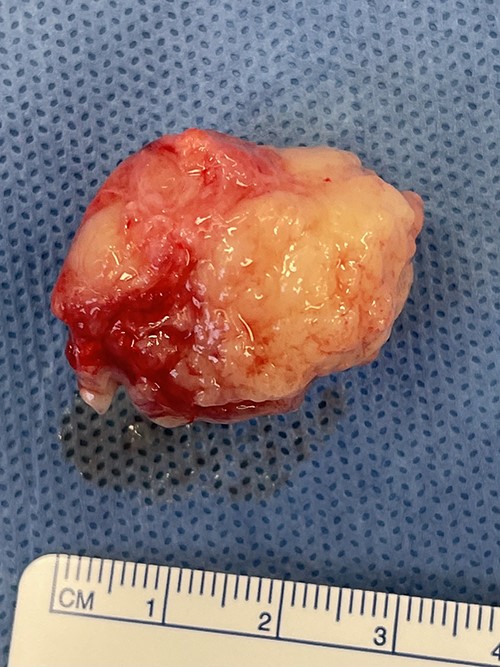

The gross specimen was a 30 × 23 × 20 mm tan fibrofatty mass (Fig. 3). Microscopically, skeletal muscle fibres were infiltrated by epithelioid tumour cells with abundant, pale, eosinophilic cytoplasm and mildly pleomorphic hyperchromatic nuclei with inconspicuous nucleoli. Patchy pseudoacini and rosette formation were present, with increased apoptosis and geographic necrosis. No lymphovascular or perineural invasion was seen (Fig. 4).